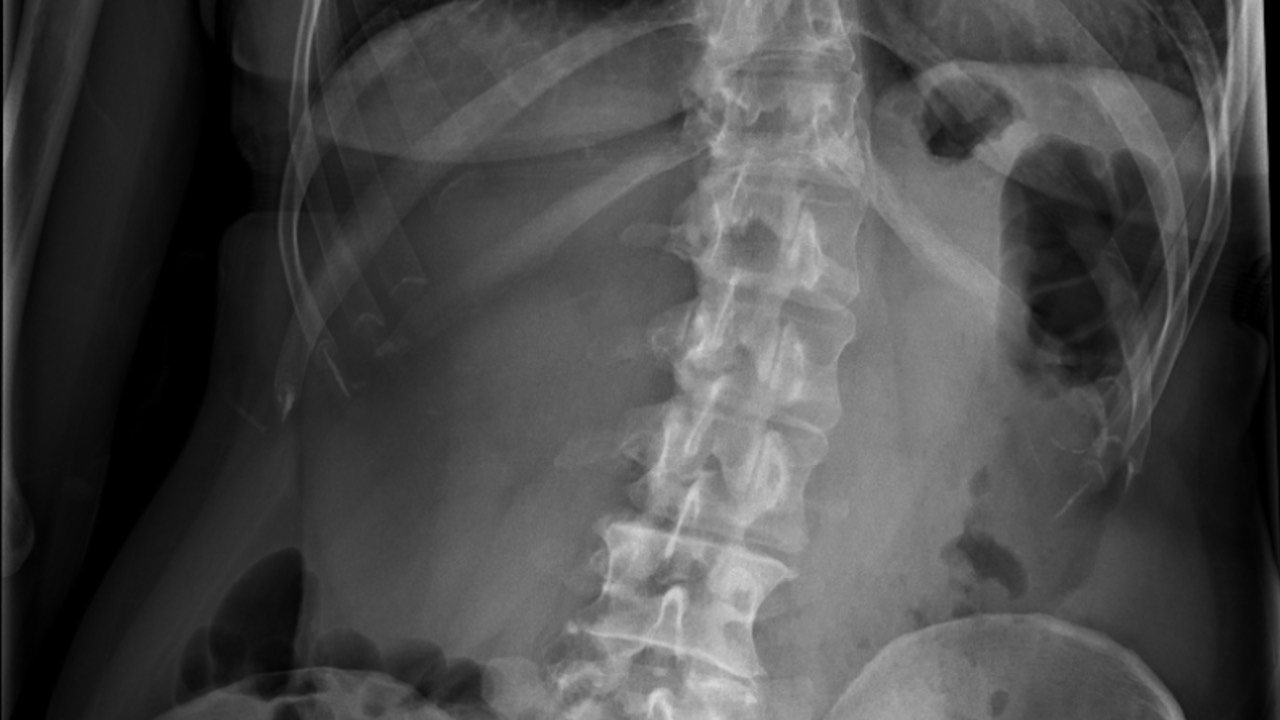

Mirroring: An Introduction to Scoliosis

This three hour distance learning course focuses on the verbiage and approach when finding the connection between the healing process of the body and mind with a Chronic Pain client/patient (specifically a Scoliotic).

1. Defining Scoliosis and Manual Cueing.

2.Define Scoliosis and the physical challenges that come along with it.